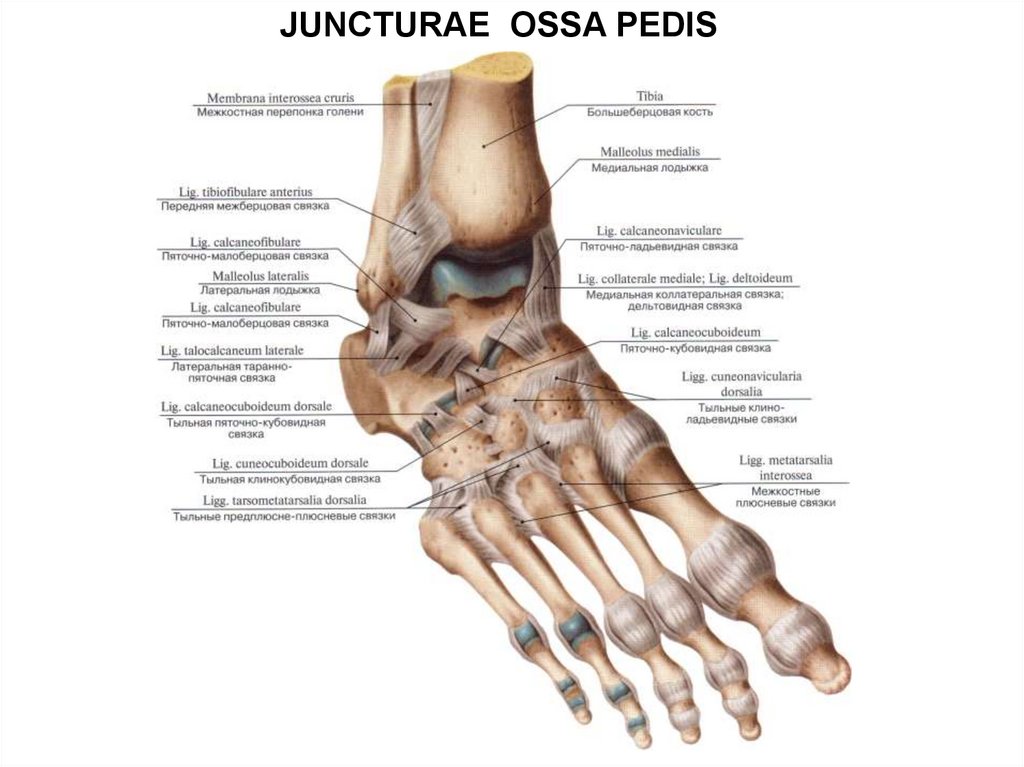

Анатомия суставов Шапарова и Лисфранка: фото и информация